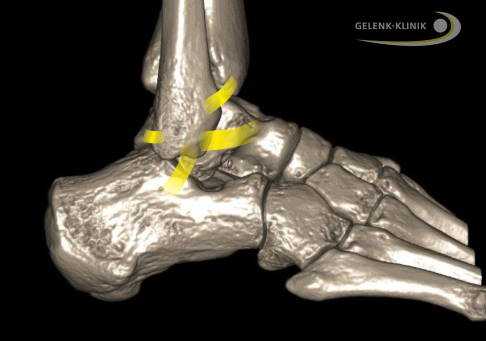

Внешние связки соединяют малоберцовую кость (Fibula) с пяточной и таранной костями. Межберцовый синдесмоз проходит между большеберцовой и малоберцовой костями. © Gelenk-Klinik